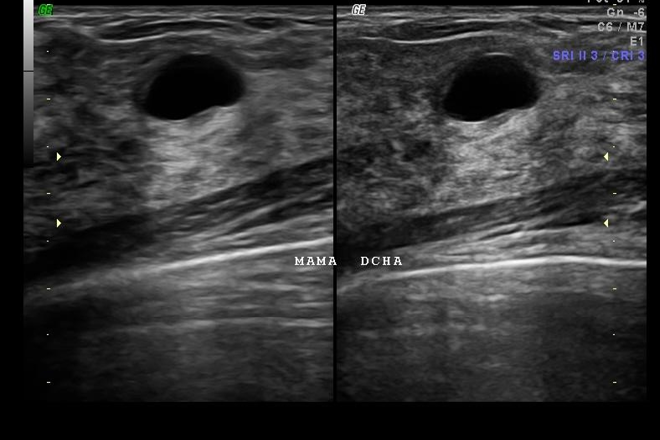

Síndrome de ovario poliquístico

Síndrome de ovario poliquístico Los criterios iniciales para el diagnóstico de síndrome de ovario poliquístico fueron (en orden de importancia): 1) hiperandrogenismo o hiperandrogenemia, 2) oligoovulación, 3) exclusión de otros trastornos conocidos, y quizá, 4) ovarios poliquísticos al ultrasonido (controversial). Años más tarde se modificaron a: 1) oligoovulación o anovulación,